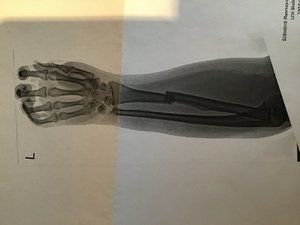

Am 12.10. habe ich mir bei einem Verkehrsunfall mit dem Fahrrad die Elle im linken Unterarm und ein Teil vom Handgelenk gebrochen.

Die Bilder sind schon sehr krass.